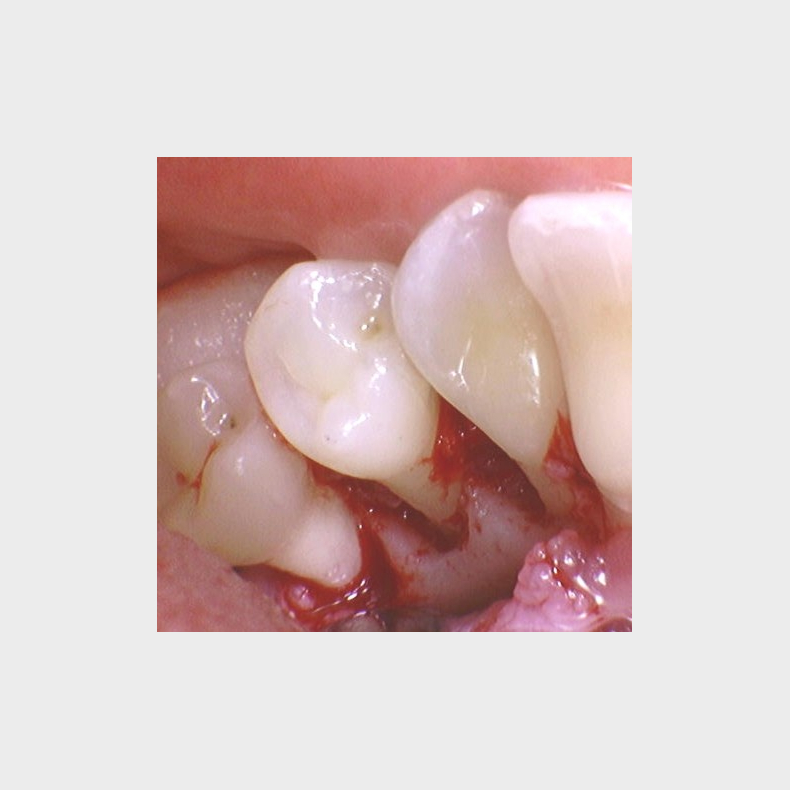

• Patientvurdering og parodontal diagnostik

• Systematisk journaloptag, risikovurdering og kliniske målinger